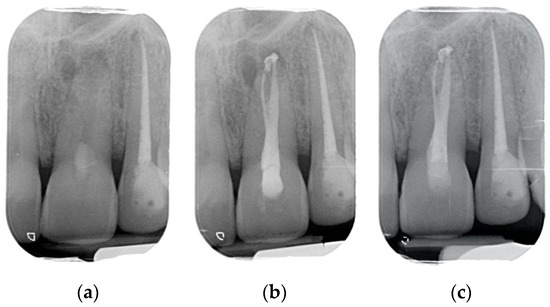

Results showed that 92.61% of ETT did not have any complications up to 18 years (Figure 1, Figure 2 and Figure 3).

Regarding the quality of root filling, 264 teeth (88.59%) showed good filling (Figure 1, Figure 2 and Figure 3) (gutta-percha at the radiologic apex), 22 roots (7.38%) short filling (shorter than 1 mm from the radiographic apex), and 12 (4.03%) long filling (longer than 1 mm of the radiographic apex).

The survival rate of both “failure” and “free of the event” of endodontically treated teeth, determined by the Kaplan–Meier analysis over an 18-year period, is shown in Figure 4 and Figure 5. The survival rate after 18 years was 97.3% (Interval of Confidence (IC) 95.1–98.3). All of the extractions, except one, occurred during the first 2 years of service. The cumulative survival to any complication displays that they occurred in the vast majority during the first 5 years of service. Notwithstanding after 18 years of observation, the success rate was 92.6% (IC 90.1–94.71).

Figure 4. The survival rate after 18 years was 97.3% (Interval of Confidence (IC) 95.1–98.3). All of the extractions, except, one occurred during the first 2 years of service.

Figure 5. The cumulative survival to any complication displays that they occurred in the vast majority during the first 5 years of service. Notwithstanding, after 18 years of observation, the success rate was 92.6% (IC 90.1–94.71).

The numbers of failures due to tooth fractures, endodontic, periodontal, or prosthodontic reasons, were limited to 22 of 298 ETT. Of the recorded failures, 14 were reported as repairable; eight were catastrophic failures and, consequently, needed root extraction. The success rate was around 92% (Figure 1, Figure 2 and Figure 3), the survival rate around 4.69%, and only less than 2.69% were irreversible failures. The success and survival rates of this clinical study were a little higher than several others [36,37,38]. Another important aspect related to the failure was the fact that irreversible failures mainly took over in the first two years and within the first 5 years, when cumulated as reversible and irreversible failures. It can be speculated that “biological” complications can come out rather quickly, and periodontal and prosthodontic complications in a longer time, but after 5 years of clinical service, it can be expected that an ETT can stay in clinical service for many more years.